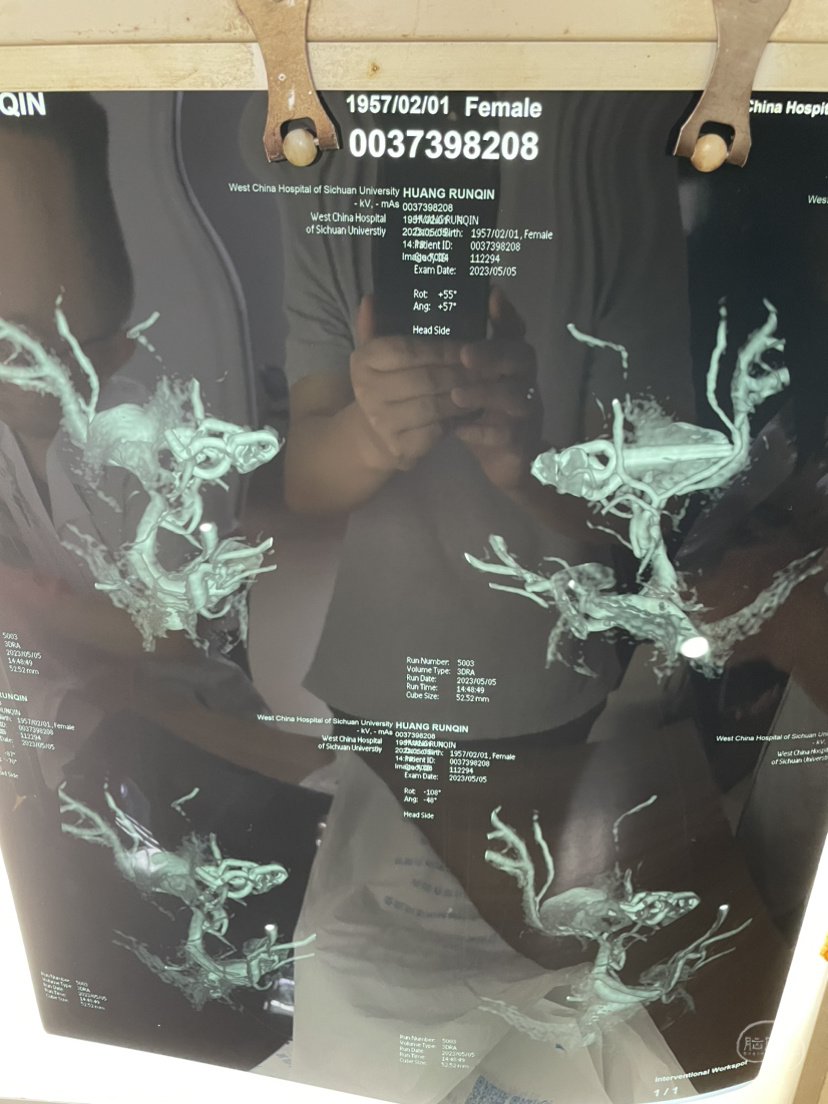

夹闭术后两个月,出院后一个月!再次出血,血肿量大,患者清醒!转上级市级医院,拟予介入栓塞后清除血肿

家属选择保守治疗,患者一直清醒!两个月前在华西行介入栓塞术,血肿吸收!